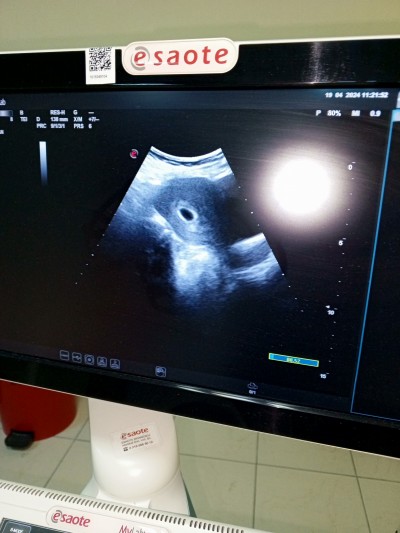

Adet tarihime göre 6 haftalık olması lazım 4 haftalık dedi . Kahverengi lekelenme tarzında akıntım da var baya

Sizce geç döllenme olmuş olabilir mi

Sonradan duzeliyormu düşük yapacağım diye korkuyorum doktor progestan başlattı

Birde ufak çaplı kist olduğunu söyledi acaba kanama bu bu yüzden olabilir mi

Evet olabilir benimde adet tarihime göre 6 haftalık tı ama ultrasonda 4 görünüyordu ama benim her hangi bir lekelenme vs yoktu kist bende de var bir tane ama yumurtalıkta dedi doktor bi sıkıntı olmaz dedi